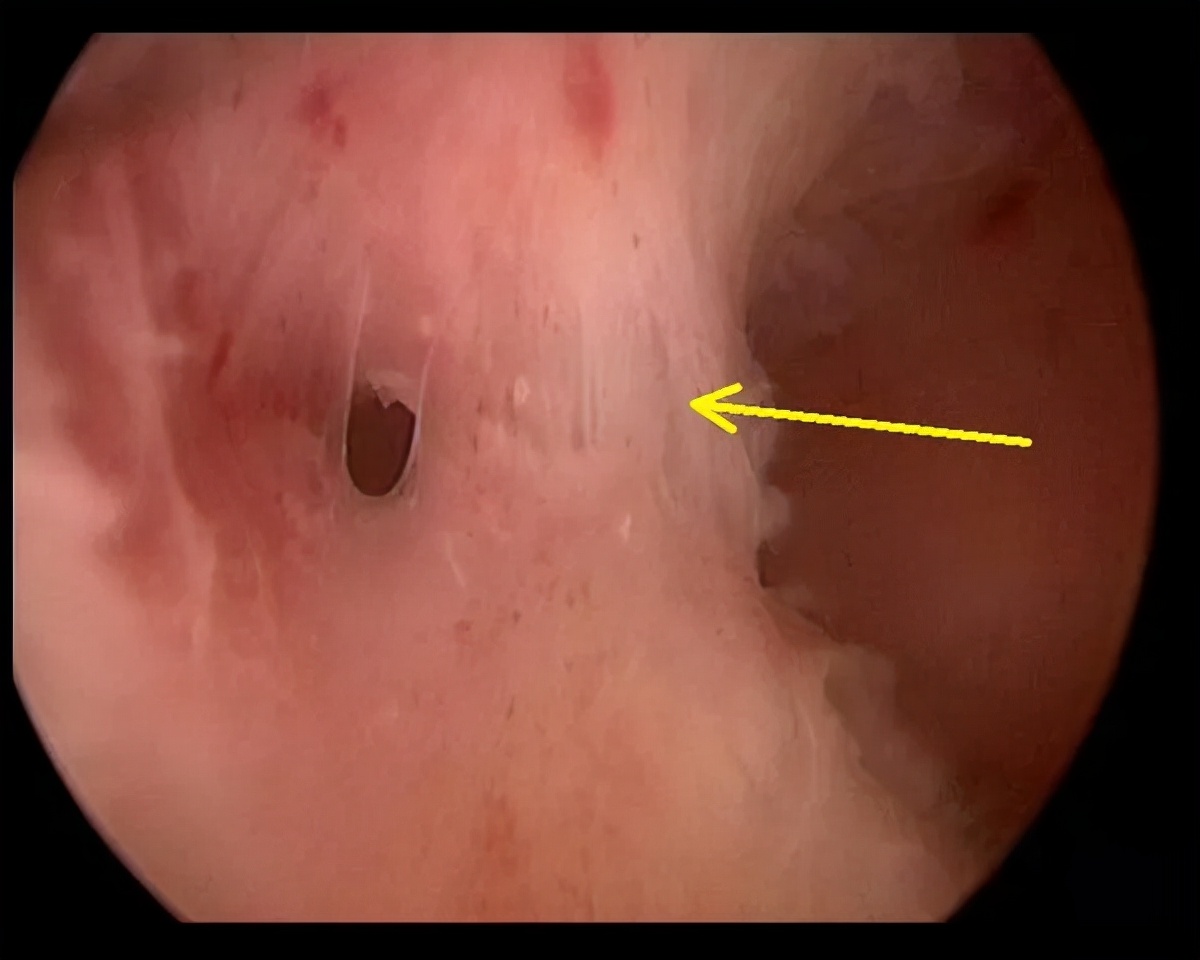

4.宫腔粘连

但是,这些疾病不都是单独存在的,有些患者可能同时几种疾病共存,共同引起异常子宫出血。